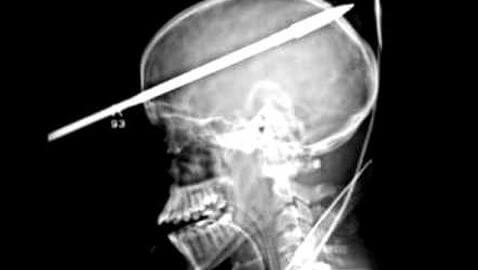

Yasel Lopez was fishing with a friend in Miami when something terribly wrong happened. Yasel, 16, had his head pierced with a spear when a spear gun fired unexpectedly. The accident occurred two weeks ago and doctors are calling Lopez’s survival a miracle. The gun accidentally fired when the two teenagers were loading it with a spear. The force of the spear impact knocked Lopez into the water because it was so strong. The friend called 911 and Lopez was transported via air to Miami’s Jackson Memorial Hospital. On Monday, doctors discussed the incident and what it took to save Lopez’s life.

“We used a high-speed drill to drill the bone at either end to create an opening through which we could remove the spear,” one doctor said in front of reporters. The spear had to be cut first in order to prevent it from moving and to also allow doctors to perform tests. Once the spear was cut, the doctors were able to perform surgery on Lopez. “We were able to position him laying with his left side down, right side up, and then we were able to open a large incision.”

As of Monday, Lopez was only able to speak to his doctors in short sentences and is still in recovery. Doctors think that Lopez is suffering from post-traumatic amnesia, which means he might not remember the accident. There were three things that kept Lopez alive throughout the ordeal. Those three things include the side of this head that the spear penetrated, that the spear missed major blood vessels and that the spear did not damage vital brain structures.